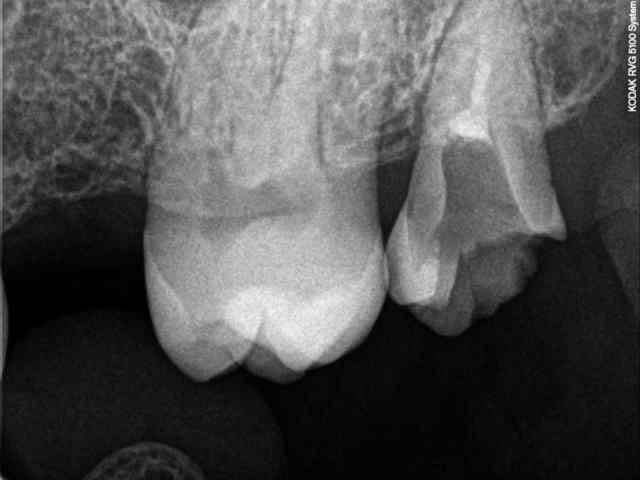

Illustration de la pertinence d'un status sur un risque carieux pourtant faible. Réalisé ce matin sur un nouveau patient. Ras à l'examen endo-buccal.

> Illustration de la pertinence d'un status sur un risque carieux pourtant faible.

> Réalisé ce matin sur un nouveau patient. Ras à l'examen endo-buccal.

Tu ne vas quand même pas lui faire des soins conservateurs??? On vaut mieux que ça quand-même. Ne casse pas la baraque de tes confrères! Attends un peu pour assurer ta fidélisation.